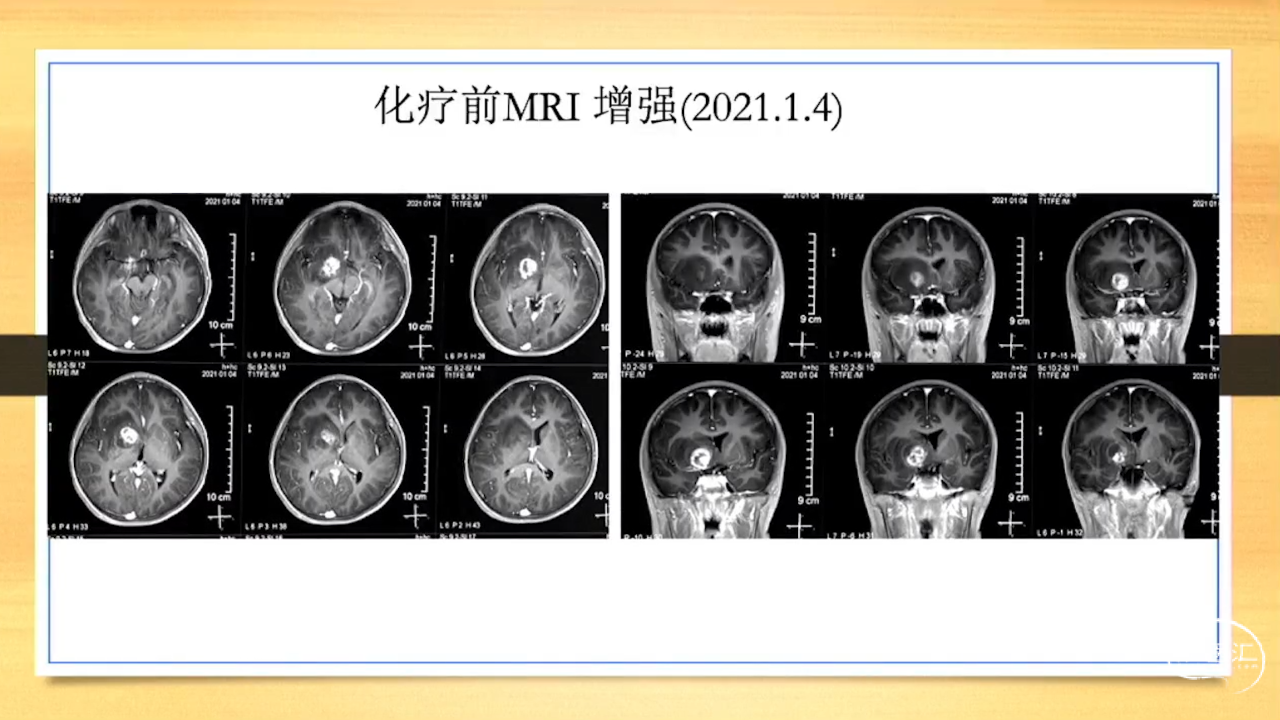

张荣教授:儿童颅内生殖细胞瘤的手术治疗

颅内生殖细胞肿瘤的治疗是手术、放疗、化疗、内分泌及其他多学科的整合治疗。及时、精准、合理的手术治疗是iGCT患者提高生存率、降低并发症、改善神经内分泌功能的关键。